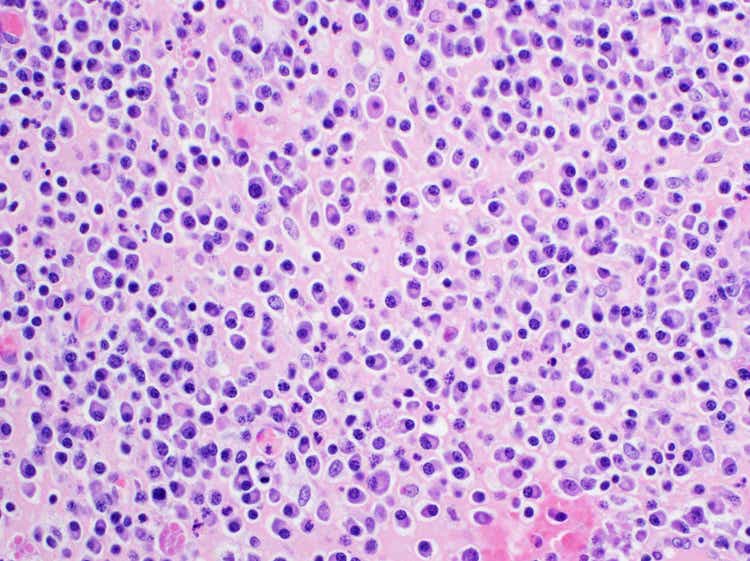

Multiple Myeloma

Survival outcomes in multiple myeloma have significantly improved thanks to decades of treatment advances. With more than half of the 11 innovative therapies approved for its treatment in the past two decades, Johnson & Johnson has helped transform patients’ lives with numerous approved innovative treatments. We aim to develop curative therapies, with urgency, and shifting the treatment paradigm from “treat-to-progression” to “treat-to-cure”.

B-cell malignancies

More than a decade ago, we co-developed and delivered a globally approved, first-in-class treatment for certain B-cell malignancies, including chronic lymphocytic leukemia, previously treated mantle cell lymphoma, Waldenström’s macroglobulinemia, and previously treated marginal zone lymphoma.

Myeloid malignancies

We are committed to bringing forth new treatment options for patients with acute myeloid leukemia (AML) and myclodysplastic syndrome (MDS) and have advanced a comprehensive development program with novel bispecific approaches as well as other novel targets with transformational potential.